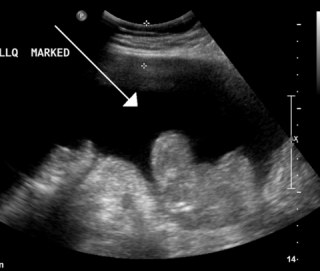

Сам процесс манипуляции происходит в условиях стационара в специально оборудованном помещении. Лицо, указанное в брюшной полости УЗИ снимает одежду, закрывающую тело и принимает горизонтальное положение, лежа на спине. Затем врач вводит увлажняющий агент на коже, состоящий из медицинского геля, который имеет повышенную проводимость сигнала высокой частоты. Эпителий смазан именно в этой части, в которой изучали внутренний орган расположен

Затем зонд наносят на кожу, который излучает ультразвуковые волны, подходящие, которые отражаются и возвращаются в виде комплексного сигнала с информацией о местоположении всех тканей и органов внутри брюшной полости. Все эти данные записываются на компьютерном устройстве, а также отображается на мониторе в трех измерениях. Продолжительность всех манипуляций не превышает 15-20 минут. В большинстве случаев, это намного быстрее, особенно, если человек не имеет каких-либо серьезных симптомов, которые с самого начала указывали бы на развитие тяжелой болезни.